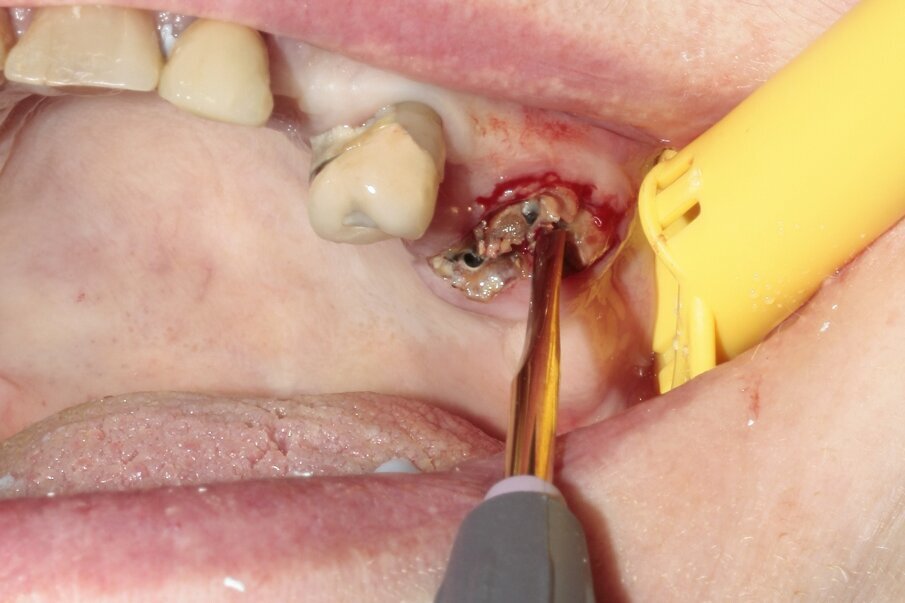

Fig. 2: The roots were separated to the correct depth. The tooth was divided into three parts to facilitate extraction.

Fig. 3: The tooth was luxated with Luxator P4 (dual edge, lilac).